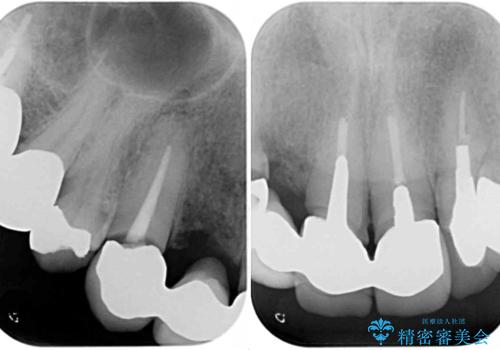

- 前歯のブリッジのセラミックが欠けてしまい、作り直したいとのことで来院された患者様です。

犬歯はブリッジの中で虫歯が進行していたため、根管治療からやり直しをした後、オールセラミックブリッジにて補綴することとしました。